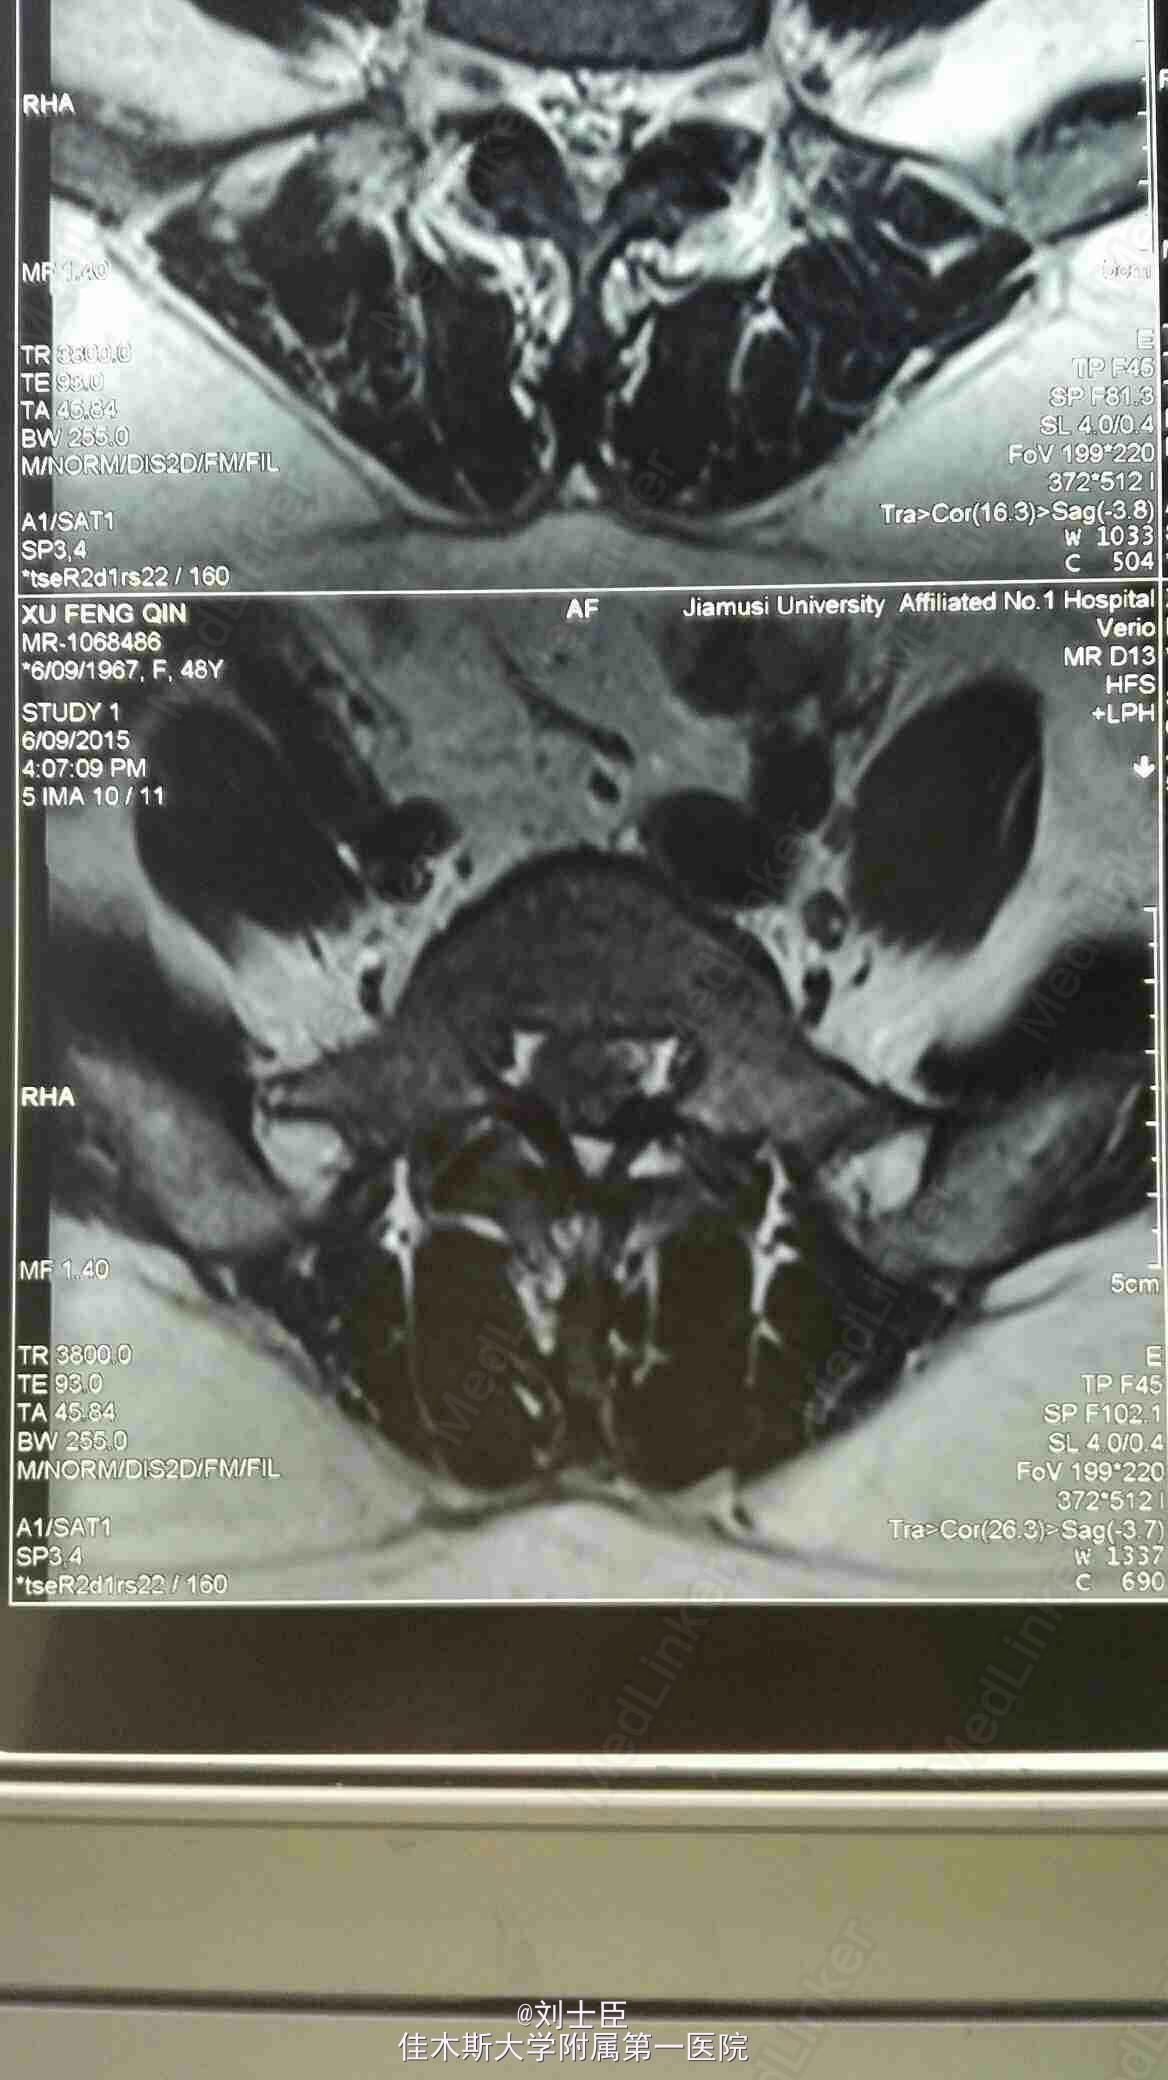

某某,女,43岁。腰痛伴双下肢疼痛1年伴二便失禁7天。

双侧小腿外侧双足及双臀部感觉麻木,双膝反射弱,双踝反射为引出。双下肢肌力进正常。

腰5骶1间盘突出症。马尾综合征。椎间孔镜下游离间盘摘除术纤维环成形术。

病人术后即可刻下地行走自如,直腿抬高实验阴性。3天后拔出尿管,二便正常,双下肢和臀区感觉麻木减轻。